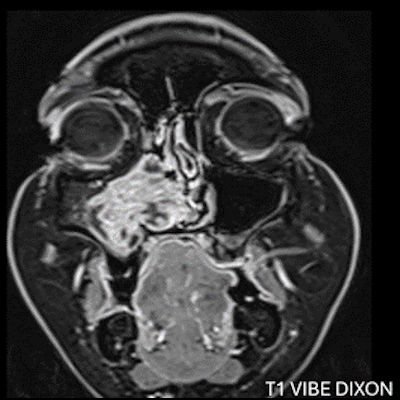

- A) Koronal T2 ağırlıklı görüntülerde sol maksiller sinüs lümenini dolduran, belirgin ‘convoluted’ (karmaşık-kıvrımlı) serebriform patern sergileyen lezyon (oklar), kontrastlı seride heterojen ve yoğun kontrastlanma göstermektedir (oklar). Perfüzyon incelemesinde pedinkülünde perfüzyon artışı gösterdiği, diğer kontrastlanan segmentlerin nispeten hipoperfüze olduğu görülmektedir (ok).

- Tümörün köken aldığı bölgede fokal hiperostoz görülebilir. Sinüs duvarlarında erozyon olabilir ancak bu genellikle tümör basısına veya eşlik eden inflamasyona sekonderdir, direkt invazyon kesin değildir. Kalsifikasyon beklenen bir bulgu değildir (olursa atipi veya malign transformasyon akla getirilmeli)

- MR incelemesinde sinonazal inverted papilloma tipik olarak T2 ve post-kontrast T1 serilerde ‘convoluted’ serebriform paternde heterojen sinyal ve kontrastlanma gösteren, pedinküler orijininde daha belirgin perfüzyon artışı sergileyen, genellikle difüzyon kısıtlaması izlenmeyen ve komşu sinüs duvarlarında ekspansiyona bağlı remodelinge yol açabilen benign ancak lokal agresif karakterde bir yumuşak doku kitlesi olarak izlenir.